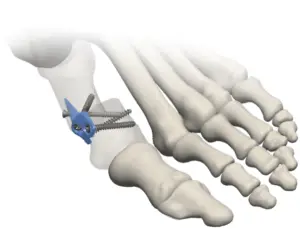

The Minimally Invasive Bunion (M.I.B.) Plating System is a unique approach to triplanar hallux valgus correction. The M.I.B. plate minimizes soft tissue disruption by only requiring a small medial incision and provides a quick, solid construct.

- The M.I.B. assembly allows for simultaneous correction in the frontal, transverse, and sagittal planes by utilizing a transverse osteotomy

- Multi-directional compression and stabilization of the osteotomy is achieved by using 2.4mm distal locking screws in conjunction with two anti-rotational, crossing, interfrag screws

- The titanium plate masks the osteotomy for minimal, medial palpability through the transition between the distal shoulder and proximal intramedullary spade